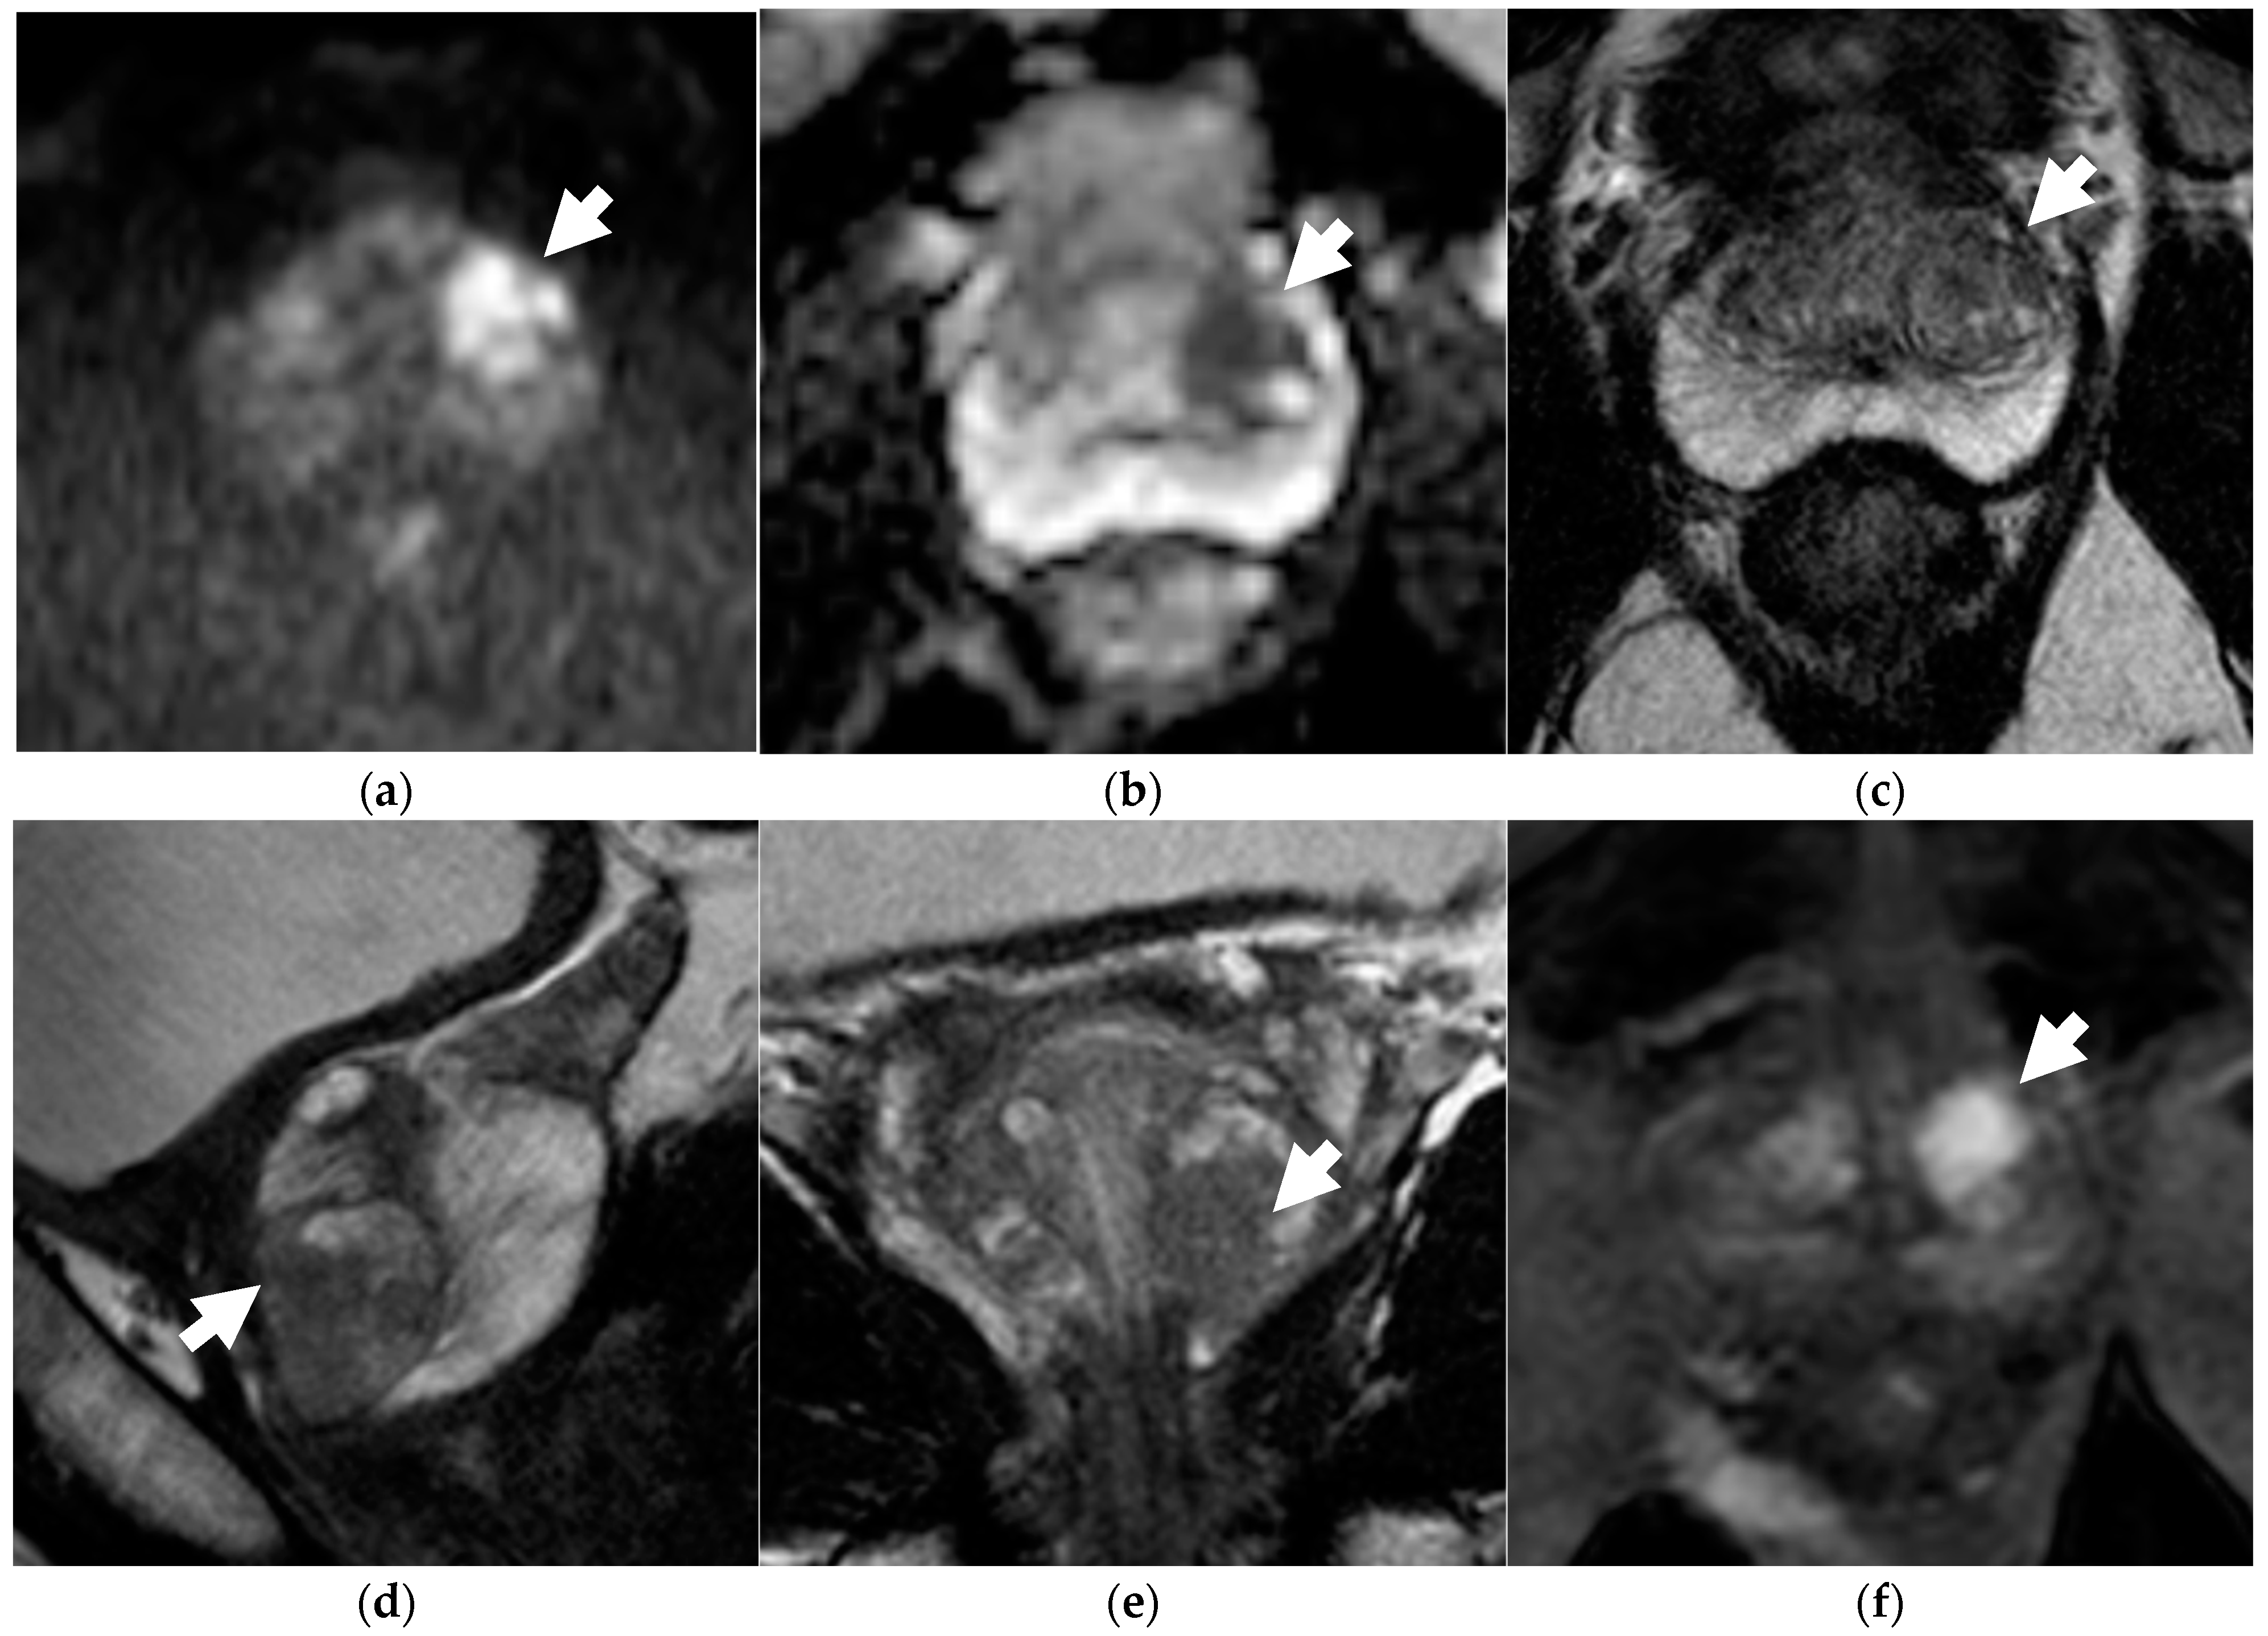

2.2. MRI Protocol

2.3. Image Analysis